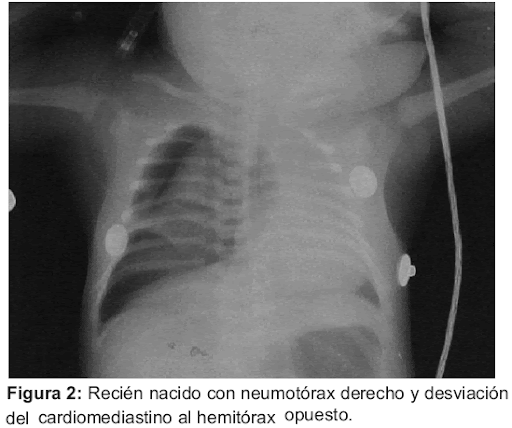

NEUMOTÓRAX

Images?Q=Tbn:A Nd9 Gc Q0 Q64 H Lqf8 Ad Rp S Wtpc Efbcm8h8m Kyo Bkw&Usqp=Cau (image/jpeg)